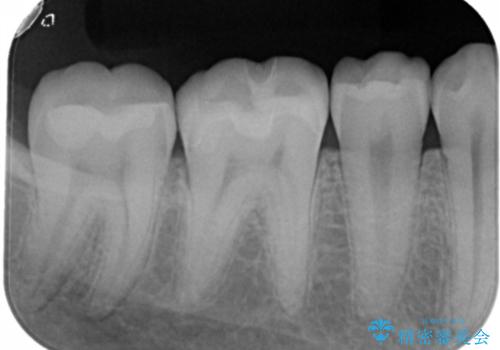

- 右下6・7番の虫歯治療を主訴に来院された患者様です。

精度が高く見た目が良いものを希望されたので、切削量・形態を考慮しセラミックインレーでの治療を計画しました。